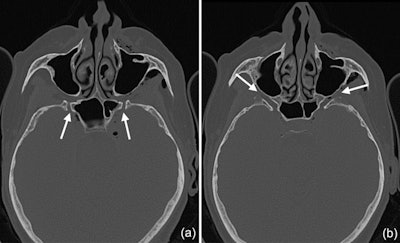

CT scans show that the pterygoid canal (a) and the forum rotundum (b) may be possible entry pathways for the air to enter the intracranial space. This is especially possible within the canal leading to the foramen rotundum, where several smaller air bubbles were captured.